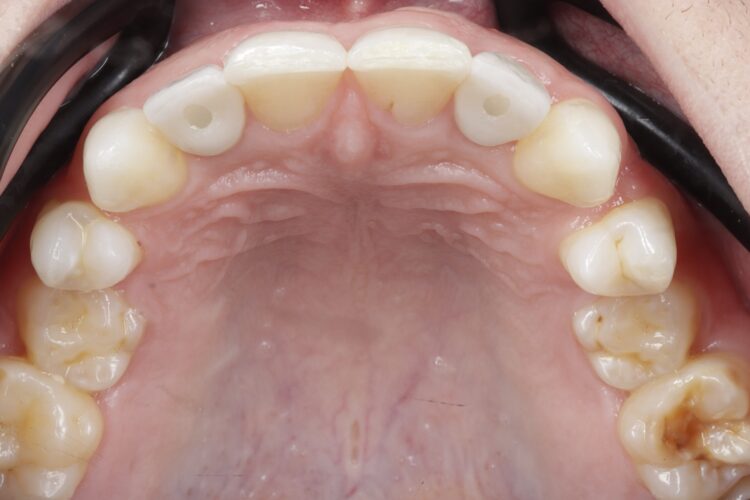

A young male presented with hypodontia and a number of missing permanent teeth. He was relatively unconcerned about his appearance and was driven more by his parents to seek treatment. As such, the patient was unsure about what he wanted from treatment and hesitant to undergo more than he absolutely needed to.

Clinical assessment

Upon assessment, it became clear that the patient’s tooth spacing was not ideal, and realignment would be necessary to create space for the lateral incisors. The patient had already been referred to me, and the option of no treatment had been discussed and ruled out. I presented the patient with two treatment options: Maryland Bridges or a combination of orthodontics and implant placement. The latter was my professional recommendation, and the patient provided informed consent to proceed, providing a clear understanding of his condition and the treatment options considered.

The patient visited the orthodontist for the first phase of treatment. Before the appliance was removed, I confirmed that the desired tooth positions had been achieved to ensure adequate spaces for implant placement.